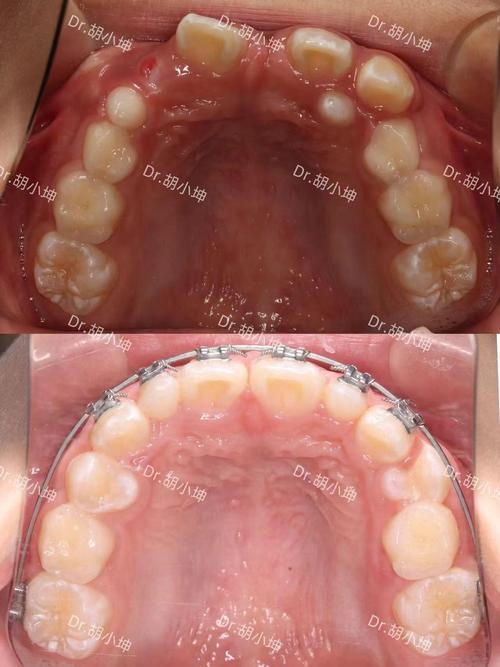

- 查看案例与资质:要求医生展示相似案例前后对比,确认机构是否具备《医疗机构执业许可证》,医生是否在卫健委官网可查。